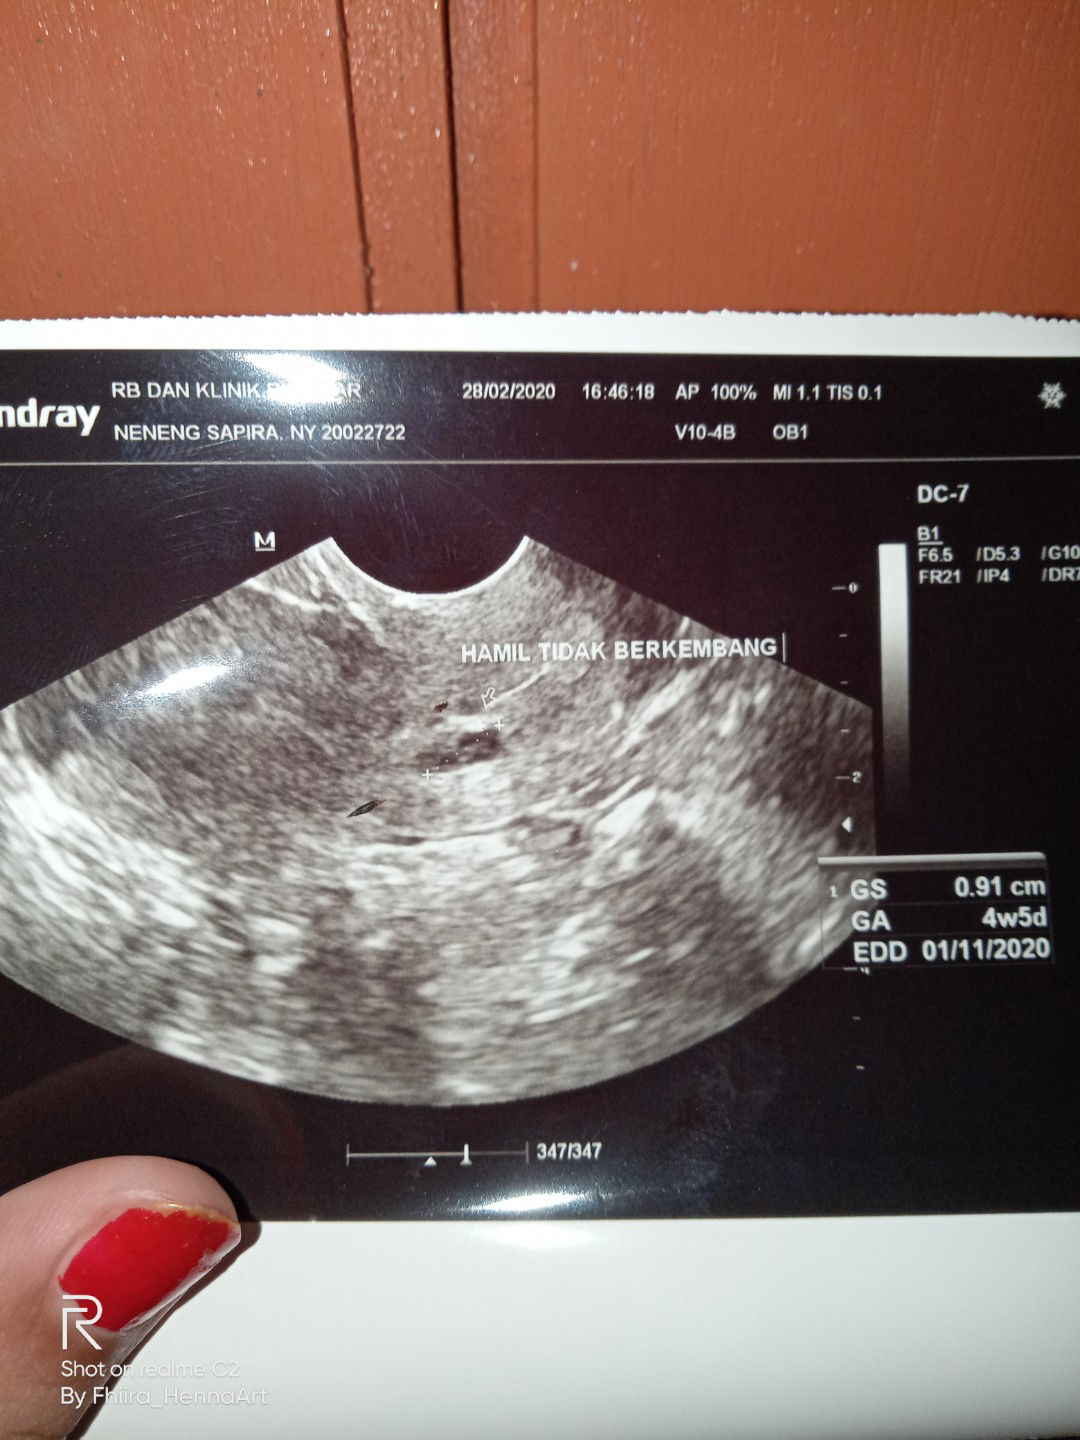

janin tidak berkembang??

Bun tdi aku usg usia kehamilan ku masuk 10w trs dokter bilang baru 4w5d janin ku tidak berkembang dokter bilang besok lgsung d kuret ??secara mendengar nya saja aku lgsung nangis d mobil seperjalanan pulang ?sya mengalami flek nmun tidak banyak hanya seujung kuku saja ituh pun hanya 3 hari kluar nya pagi saja ? kata suami dan mertua ku jgn berkecil hati dulu coba priksa ke tempat lain ?menurut bunda" Gmn solusinya apah yg harus sya lakukan mengikuti kata dokter atau coba priksa ke klinik lain?? Dan adakah yang sama kisah nya sama yg saya alami

Bun tdi aku usg usia kehamilan ku masuk 10w trs dokter bilang janin ku tidak berkembang dokter bilang besok lgsung d kuret ??secara mendengar nya saja aku lgsung nangis d mobil seperjalanan pulang ?sya mengalami flek nmun tidak banyak hanya seujung kuku saja ituh pun hanya 3 hari kluar nya pagi saja ? kata suami dan mertua ku jgn berkecil hati dulu coba priksa ke tempat lain ?menurut bunda" Gmn solusinya apah yg harus sya lakukan mengikuti kata dokter atau coba priksa ke klinik lain?? Dan adakah yang sama kisah nya sama yg saya alami